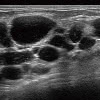

- エコーで確認しながらしこりを除去

ヒアルロン酸ならヒアルロニダーゼ、アクアフィリングなら生理食塩水を注入してしこりを溶かし、乳腺用エコーで確認しながら、注射器で吸引除去します。強い炎症でしこりが瘢痕化(はんこんか:過剰分泌されたコラーゲンが沈着)している場合は、切開手術を行う場合もありますが、傷跡の位置や大きさには十分配慮し、目立たないように工夫して手術を行うのでご安心ください。 -

的確にしこりへ穿刺・注入

しこりの消失を確認

目視することで確実に除去

豊胸の修正手術は、術前から術後まで必ずエコーを実施

術前は、シリコンバッグやしこりの状態を確認します。他院修正の場合は、触診ではわからない症状やバスト内の状態を確認したうえで、傷やダメージをできるだけ抑えられる除去方法を検討。ヒアルロン酸やアクアフィリング除去の場合は、術中もエコーを使用し、目視しながら的確にしこりを除去します。術後は、しこりが完全に除去できたか、同時に脂肪注入した場合は脂肪がしっかり定着しているかのチェックです。術後の仕上がりとゲストの健康状態に責任を持つために、入念なエコー検査を行っています。